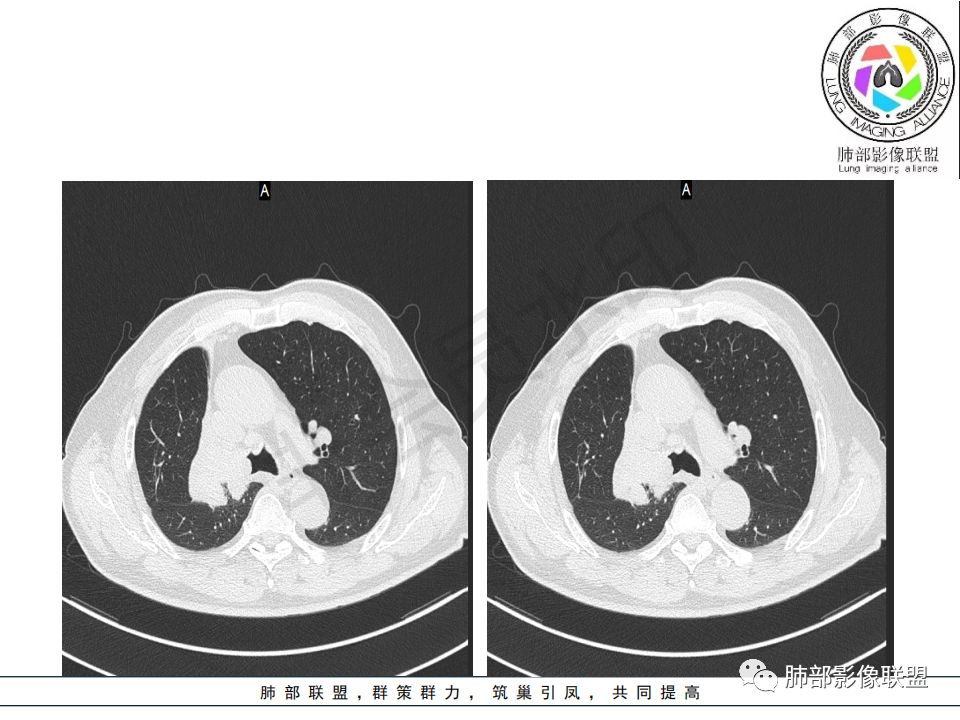

右肺主支气管有软组织肿块,向腔内外生长,右肺上叶肺不张,边缘光滑,增强扫描不均匀强化。考虑恶性肿瘤,鳞癌可能。

晨读,右肺主支气管有阻塞,腔内.腔外都见软组织影,右肺上叶不张,肿块内部密度不均匀,是不是有坏死影,老年男性,考虑恶性~鳞癌

右肺主支气管内外软组织影,支气管变窄截断,右肺上叶成软组织密度,其内见细沙样钙化,周围看见小结节,右肺门看见一淋巴结稍大,增强不均匀强化,胃癌病史,考虑:转移,或原发肺恶性鳞癌。

晨读:患者老年男性,以咳嗽一月就诊,少量白痰,胸CT:纵隔右移,右肺体积缩小,气管下段管壁可见结节样改变,气管软骨变形,气管下段及右主支气管可见新生物向管壁浸润,并向管腔外生长,右上肺肺不张,但不张边缘可见病灶呈膨胀性生长,可见分叶,增强后强化明显。考虑:肺部恶性病变(鳞癌?)

老年男性,右肺气管内软组织影,支气管变窄截断,右肺上叶阻塞性肺不张,内见细点状钙化,周围看见小结节,增强不均匀强化,考虑:原发肺恶性鳞癌。胃癌病史,转移不出外。鉴别神经内分泌癌,类癌。

晨读病例:老年男性,症状轻,右侧胸廓略塌陷,右肺主支气管内外软组织影,支气管变窄截断,右肺上叶不张,其内见细砂样钙化,周围看见小结节,右肺门看见一淋巴结稍大,增强不均匀强化,胃癌病史,常规考虑:转移,或原发肺恶性鳞癌。鉴别支气管TB?